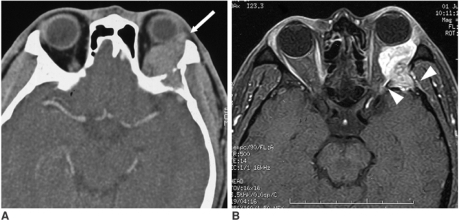

- CT: 골 침범, 석회화 평가

- MRI: 연조직 해상도 우수, 시신경 침범 평가

주요 안와종양 영상 소견

- 비축성(non-axial) 돌출: 근원추 외 종양 (눈물샘종양→하내측 편위)

- 눈물샘 종양: 상외측, 안구 하내측 편위